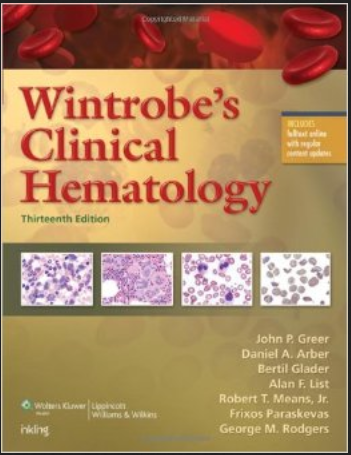

36 blood software

The poetry… in the series of codes .. B100D software bio-computer science.

The podiatry order entry .. in the series of codes of B100D

…………B100D software languages …… words, nouns, thoughts

Heme | definition of heme by Medical dictionary

Heme binds and carries oxygen in the red blood cells, releasing it to tissues. Also spelled haeme. See also hemoglobin, porphobilinogen, protoporphyrin.

Heme | definition of heme

Heme | definition of heme OUTPUT formats

Heme | definition of Theme …. SCheme